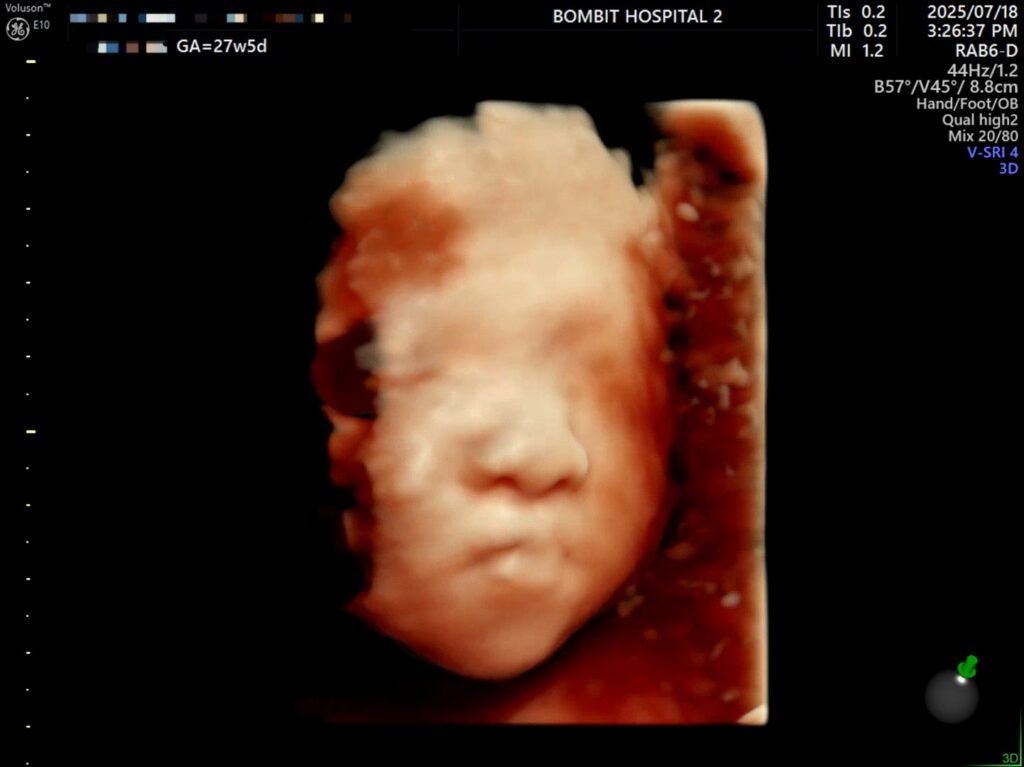

그렇게 다행스럽게도 단비 얼굴을 볼 수 있게 되었다.

체중은 상위 84%, BPD(머리 폭)이 상위 97%다. FL(대퇴골 길이)도 상위 91%..

입초로 본 단비 얼굴은 정말 너무너무 귀여웠다!! 보면서 코가 복코같이 눌려있다고 생각했는데,, 선생님은 아기 콧대가 높다고 했다. 엄마를 닮아서 그런 듯(?)ㅋㅋㅋ

오빠도 단비 사진을 보더니 너무 이쁘다고 했다. 그래서 걱정된다며..ㅎㅎㅎ